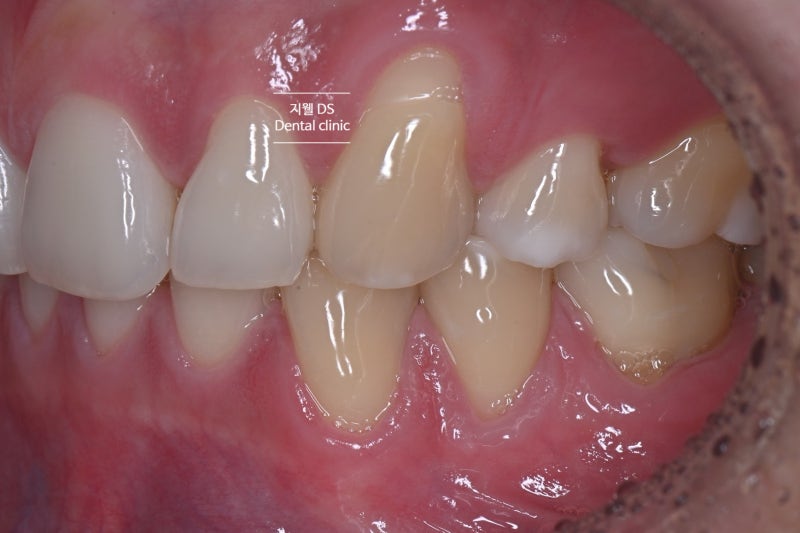

20대 남자분이세요. 교정이 끝난 지 몇 년이 지났다고 해서 잘 때 이를 가는 이야기를 들었다고 합니다. 아침에 일어나면 턱 주변과 근육 쪽이 불편하다고 해서 치아가 전체적으로 시리는데 특히 양뿔니가 굉장히 시리거든요.양치질을 할 때 칫솔이 닿아도 아파요.입을 벌리고 닫을 때는 통증이 없습니다. 라는 주소로 내원했습니다.

왼쪽 송곳니 부분 깊숙이 내려간 잇몸부 마모가 시린 증상을 일으키는 것으로 보입니다. 이를 갈면서 측방력을 많이 받아 굴곡이 생기고 그쪽에 시린 증상이 심한 것으로 판단됩니다.

교정을 하고 구치부의 신장 관계는 나쁘지 않지만 전반적으로 협측 교두가 상당히 마모된 모습입니다.